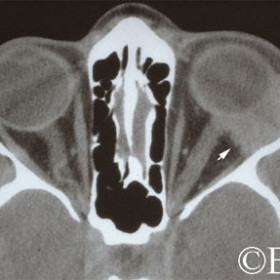

Sclerosing pseudotumor

Sclerosing pseudotumor - CT coronal image - nasal orbit- Note the irregular tumor margins.